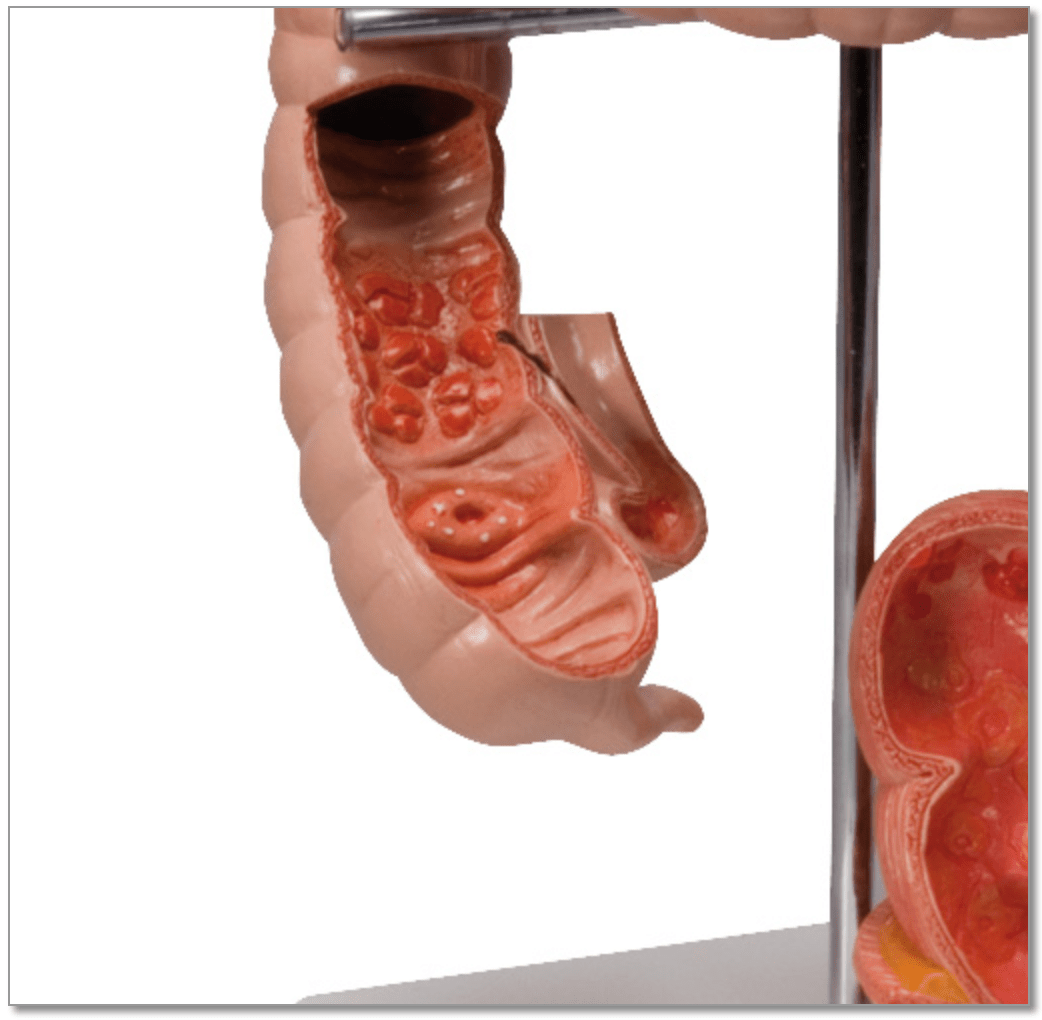

Anatomical models

Selling anatomical models is the mainstay of eAnatomi, although we also spend a lot of resources developing our own anatomical materials such as posters. Anatomical models are used for various purposes and can show both defined tissues, organs and organ systems. Are you looking for a simple model of bone tissue or perhaps an advanced torso model based on MRI technology, you can find it all at eanatomi.com.